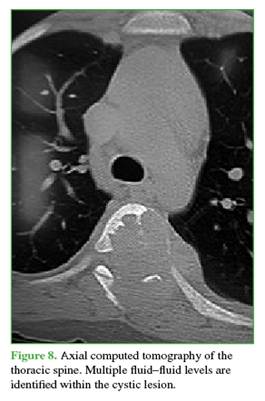

The lesion involved zones 3-6 and levels III and IV of the Weinstein-Boriani-Biagini classification.11 Complementary imaging studies showed multiple septated cysts with fluid-fluid levels. A simple bone cyst with expansile and compressive features was ruled out, as was vertebral hemangioma (Figures 7 and 8). This case was also interpreted as an Enneking grade 3 ABC.13